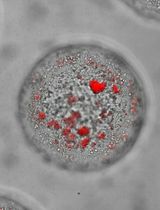

Analyze osteoclast differentiation in TRAP stained slides

Scan whole TRAP stained tissue slides with an Olympus Hamamatsu NanoZoomer whole slide scanner at 40× magnification.

Use the Freehand Line tool in the NDP.view2 software to calculate the length of the interface between tumor and bone in tibial tumor samples. If multiple interfaces exist in the samples, calculate the sum of lengths.

Count the occurrence of TRAP positive cells at the tumor and bone interface.

Calculate the average occurrence of TRAP positive cells at the tumor and bone interface.

Show representative images with higher resolution as desired (Figure 3).

Figure 3. TRAP staining in 5-week tibial tumors. Shown are representative images of 2.5× (A, B), 10× (C), and 40× (D) magnifications of a PC-3 tibial tumor sample. Scale bars in A-B: 500 µm. Scale bar in C: 100 µm. Scale bar in D: 50 µm. T, tumor tissue. B, bone tissue. BM, bone marrow. M, muscle tissue. The lengths of tumor and bone interface were calculated in B using NDP.view2.